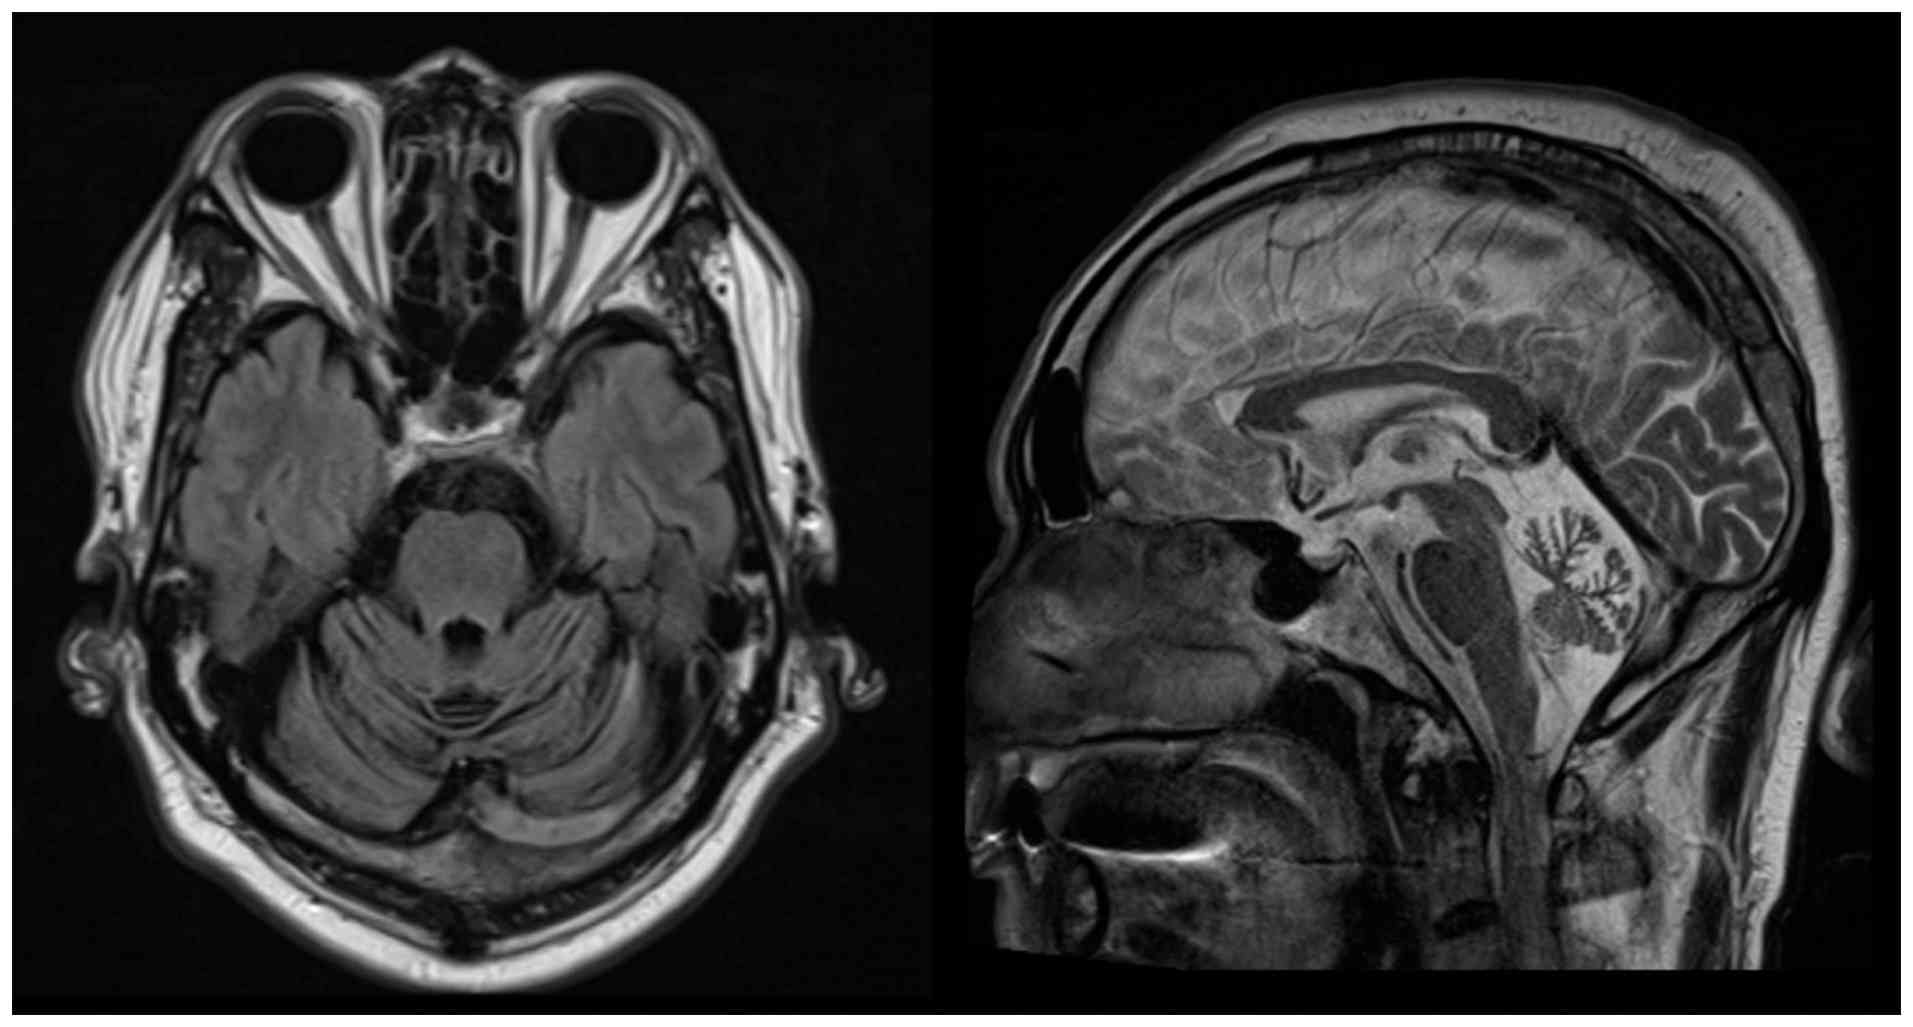

A 72-year-old male patient presented to Changhua Christian Hospital (Changhua City, Taiwan) in November 2020 with progressive gait instability that started when the patient was 40 years old. The patient had mild unsteadiness while walking, which worsened over the years. On the first visit, a neurological examination showed an unsteady wide-based gait and a positive Romberg sign with worsening instability while the eyes of the patient were closed. The patient also had bilateral mild intention tremor and dysmetria on the finger-nose-finger test. The Scale for the Assessment and Rating of Ataxia (SARA) score (10) of the patient was 8.5, with most impairment in gait and stance. Over the next few months, the patient developed mild dysarthria, slowed saccadic eye movements and numbness in the lower limbs, which was more pronounced on the left side. A sensory examination showed reduced light touch and pinprick sensation in the left lower limb. Brain MRI showed severe diffuse cerebellar atrophy with prominent cerebellar folia sulci (Fig. 1).

Brain MRI of the proband revealed

severe diffuse cerebellar atrophy.

Brain MRI of the proband revealed severe diffuse cerebellar atrophy.